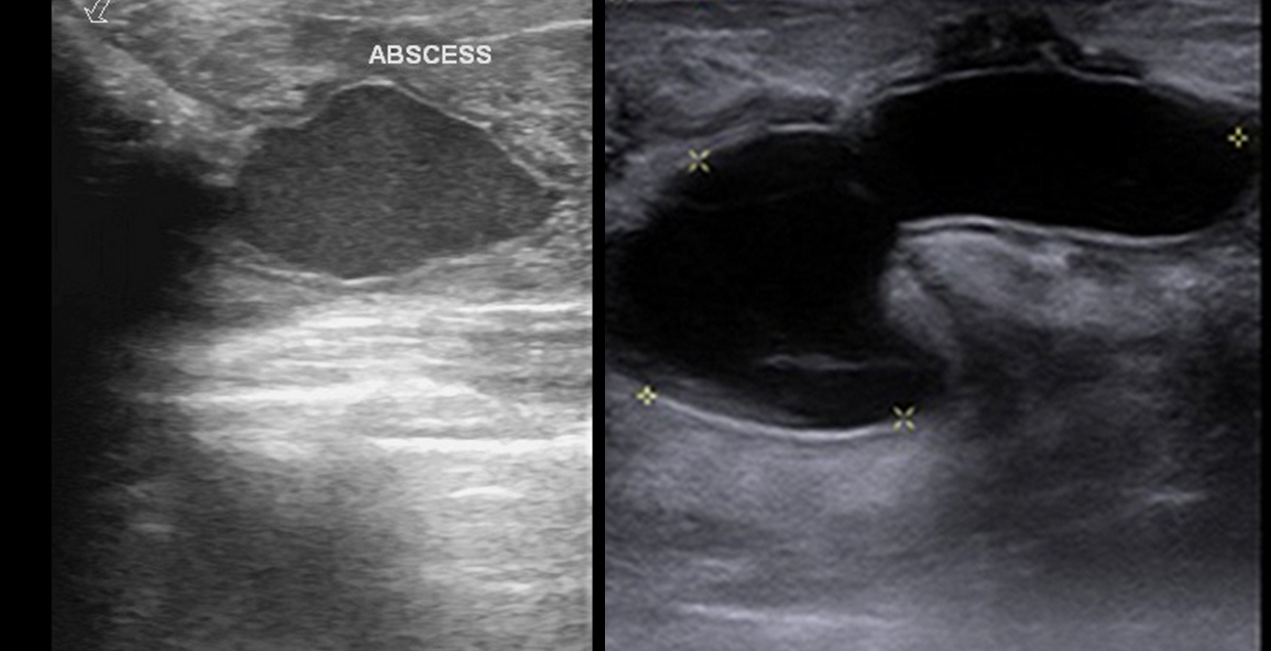

- Abscess- repeated aspiration or incision- drainage.

- Abscess- aspiration (small) or drainage (large)

Uncommon. Treated by antibiotics and aspiration/ drainage